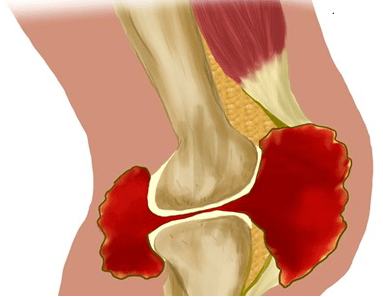

Наличие в полости колена посторонних тел приводит к развитию синовита — воспалительного процесса в синовиальной оболочке, сопровождающегося скоплением жидкости (выпота). Заболевание клинически проявляется повышением местной температуры, отечностью, покраснением кожи.

Осложнения хондроматоза без лечения

Если блокада колена происходит часто и продолжается подолгу, то это предрасполагает к тугоподвижности, формированию контрактур, а в особо тяжелых случаях — атрофическим изменениям мышц ног. Постоянное повреждение эпифизарных хрящей свободно перемещающимися внутрисуставными тельцами становится причиной развития деформирующего остеоартроза (гонартроза). Эта патология быстро прогрессирует и с трудом поддается консервативной терапии.